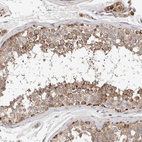

Immunohistochemical staining of human cerebral cortex shows moderate to strong cytoplasmic positivity in neurons.